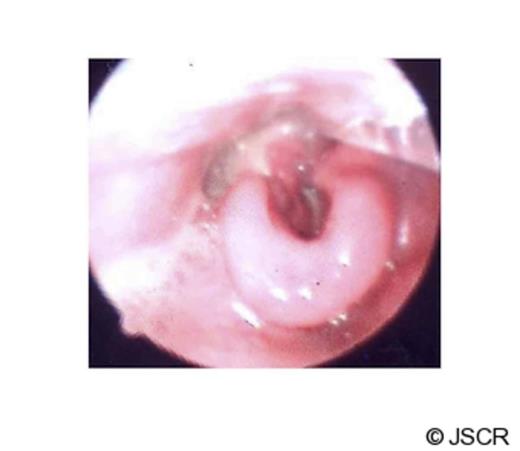

The patient was intubated in the theatre and direct laryngoscopy demonstrated an oedematous supraglottis with redundant patchy necrosis occluding the glottis. Subsequently he was transferred to Intensive Care Unit and treated conservatively with dexamethasone and antibiotics (Table 1). There was no improvement in the patient clinically or by laboratory parameters. Daily nasal endoscopy findings showed progressive supraglottic soft tissue oedema, worsening necrosis, pooling of saliva and diminishing air leak around the orotracheal tube.

On the same day, the patient was re-evaluated under general anaesthesia. Direct laryngoscopy revealed an extensive oedematous supraglottis with severe necrosis involving the laryngeal inlet, base of the tongue and right tonsillar bed. Incision of the soft tissue drained foul smelling fluid with minimal bleeding during biopsy. Surgical debridement was not possible without compromising the integrity of the larynx due to extensive necrosis. Subsequently a tracheotomy was performed with a limited exploration of the neck, showing only inflamed soft tissues in the anterior compartment. There was no evidence of necrosis or collection of pus in the neck spaces.

After the operation, the diagnosis was revised to isolated necrotizing fasciitis of the larynx. The necrosis of the larynx was closely monitored. A combination of empirical antibiotic therapy was prescribed under guidance of microbiologist (Table 1). The antibiotic regimen made significant improvements in the laryngeal oedema (Fig 2), resolution of necrosis and inflammation of the laryngopharynx.